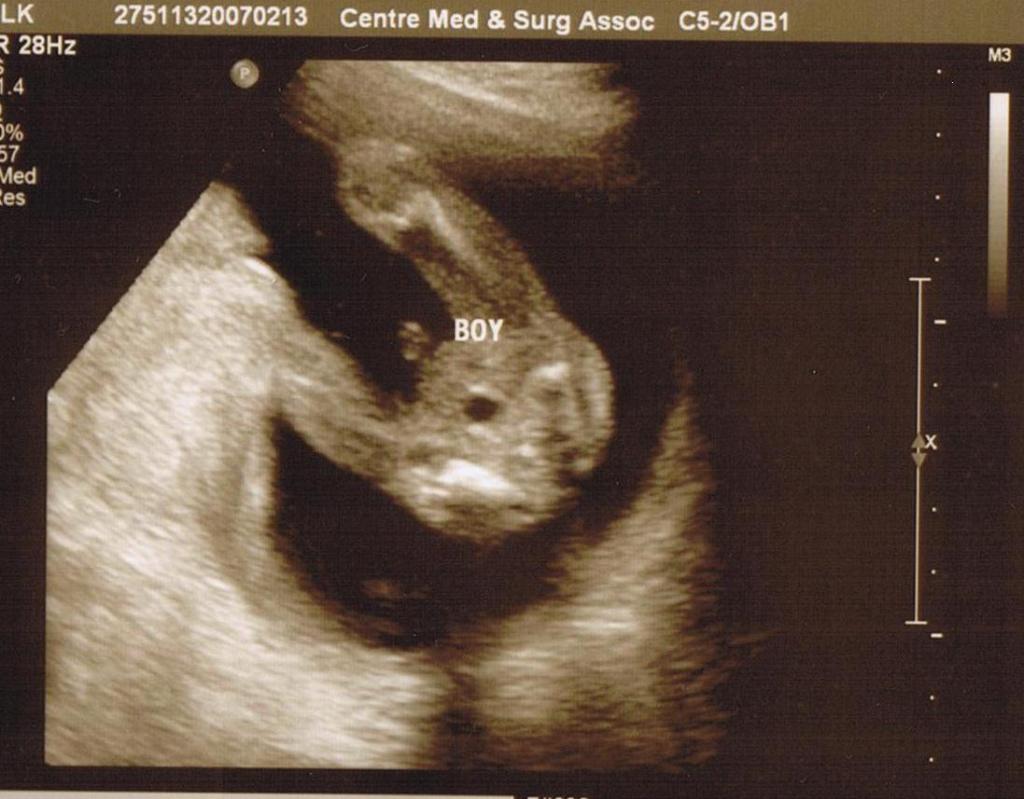

2月13日的情人節前夕, 是我跟老公大人等到脖子都長几吋的日子. 我們終於要跟寶寶作一次最詳細的接近了, 我們終於可以我們寶寶是男生還是女生了耶…….嘻…….好開心喔!

醫生看了一輪寶寶的骨骼之後, 終於問我們要不要知道寶寶的性別了. 然後就把鏡頭拉近放大, 指著寶寶的弟弟跟我們說:"this is a boy!" 哈哈哈……原來我們寶寶真的很合作, 把腳舉得高高的, 還張得大大的, 向我們show 他的弟弟耶….哈哈哈….從頭到尾都沒有藏過, 一路show 到底, 醫生就跟我們講了三, 四次—–這是寶寶的弟弟了, 哈….好可愛喔!

這几張照片蠻清楚的, 連我爸媽都會看喔, 我想大家都會看得懂吧.

第四那張是我們寶寶的小屁股喔, 醫生小姐還特意在那里注明, 看那里就知道我們是小男生了耶!!!!!!!!!